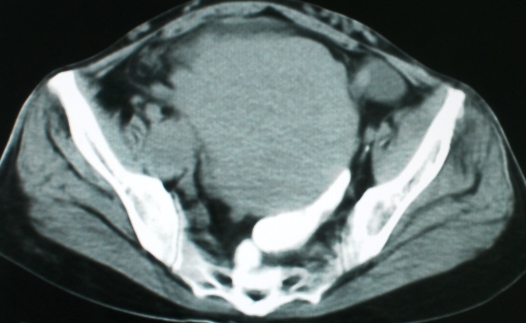

以下是引用zsl6918在2008-11-4 19:14:00的发言:[br]多发转移性改变,子宫改变不除外为原发灶